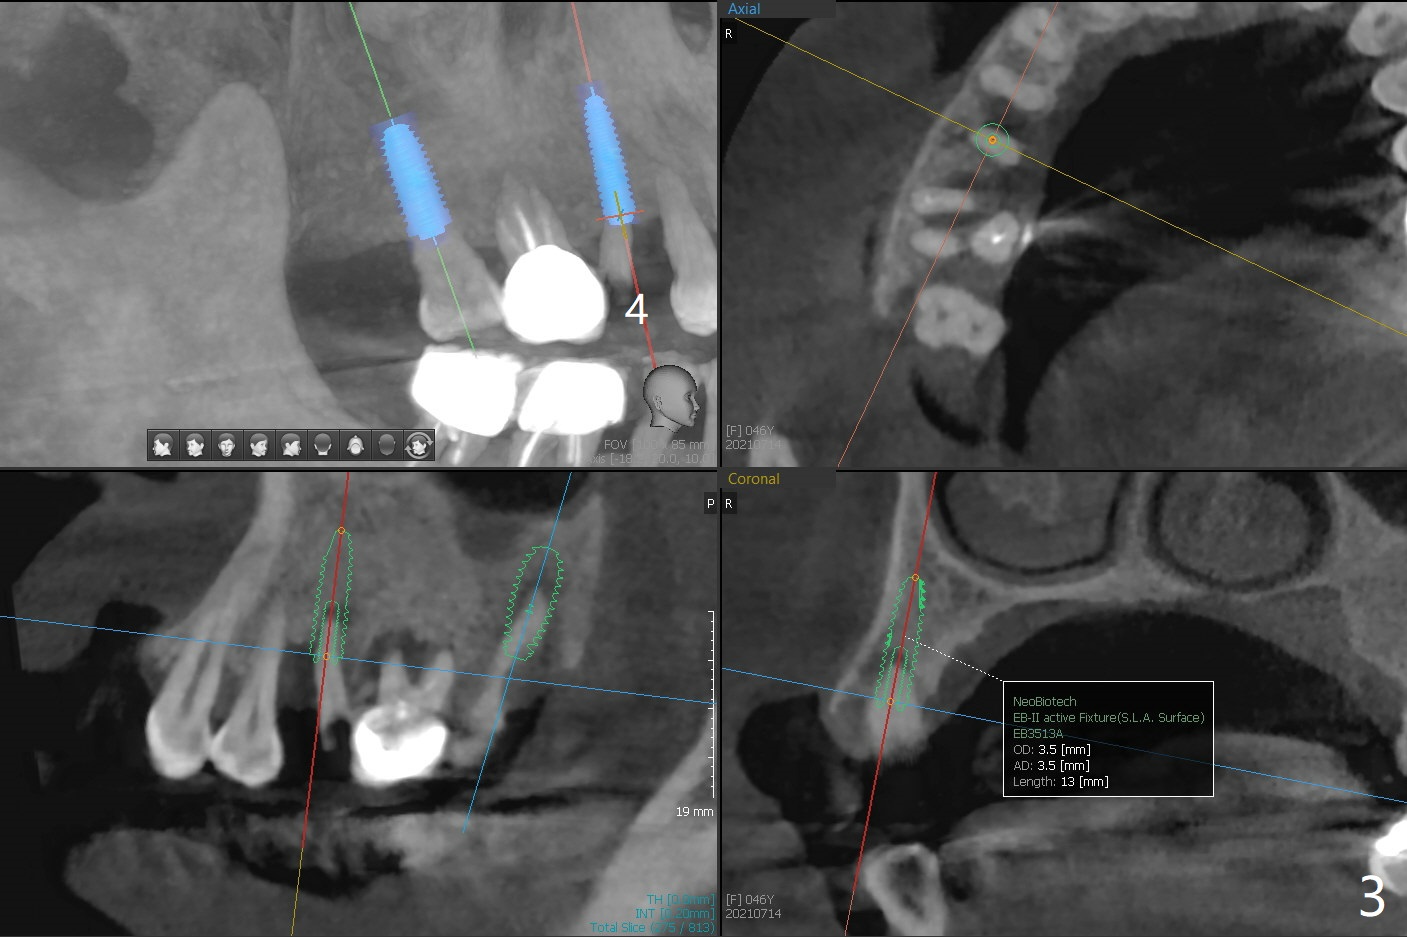

Away From Lesion

A 46-year-old woman wants to extract the mobile #2 and residual root of #4 for implants. She wants to save the tooth #3 with mobility II (Fig.1). Place an implant at #2 away from #3 (Fig.2). A small implant will be placed at #4 for the best possible trajectory (Fig.3). PRFx2.